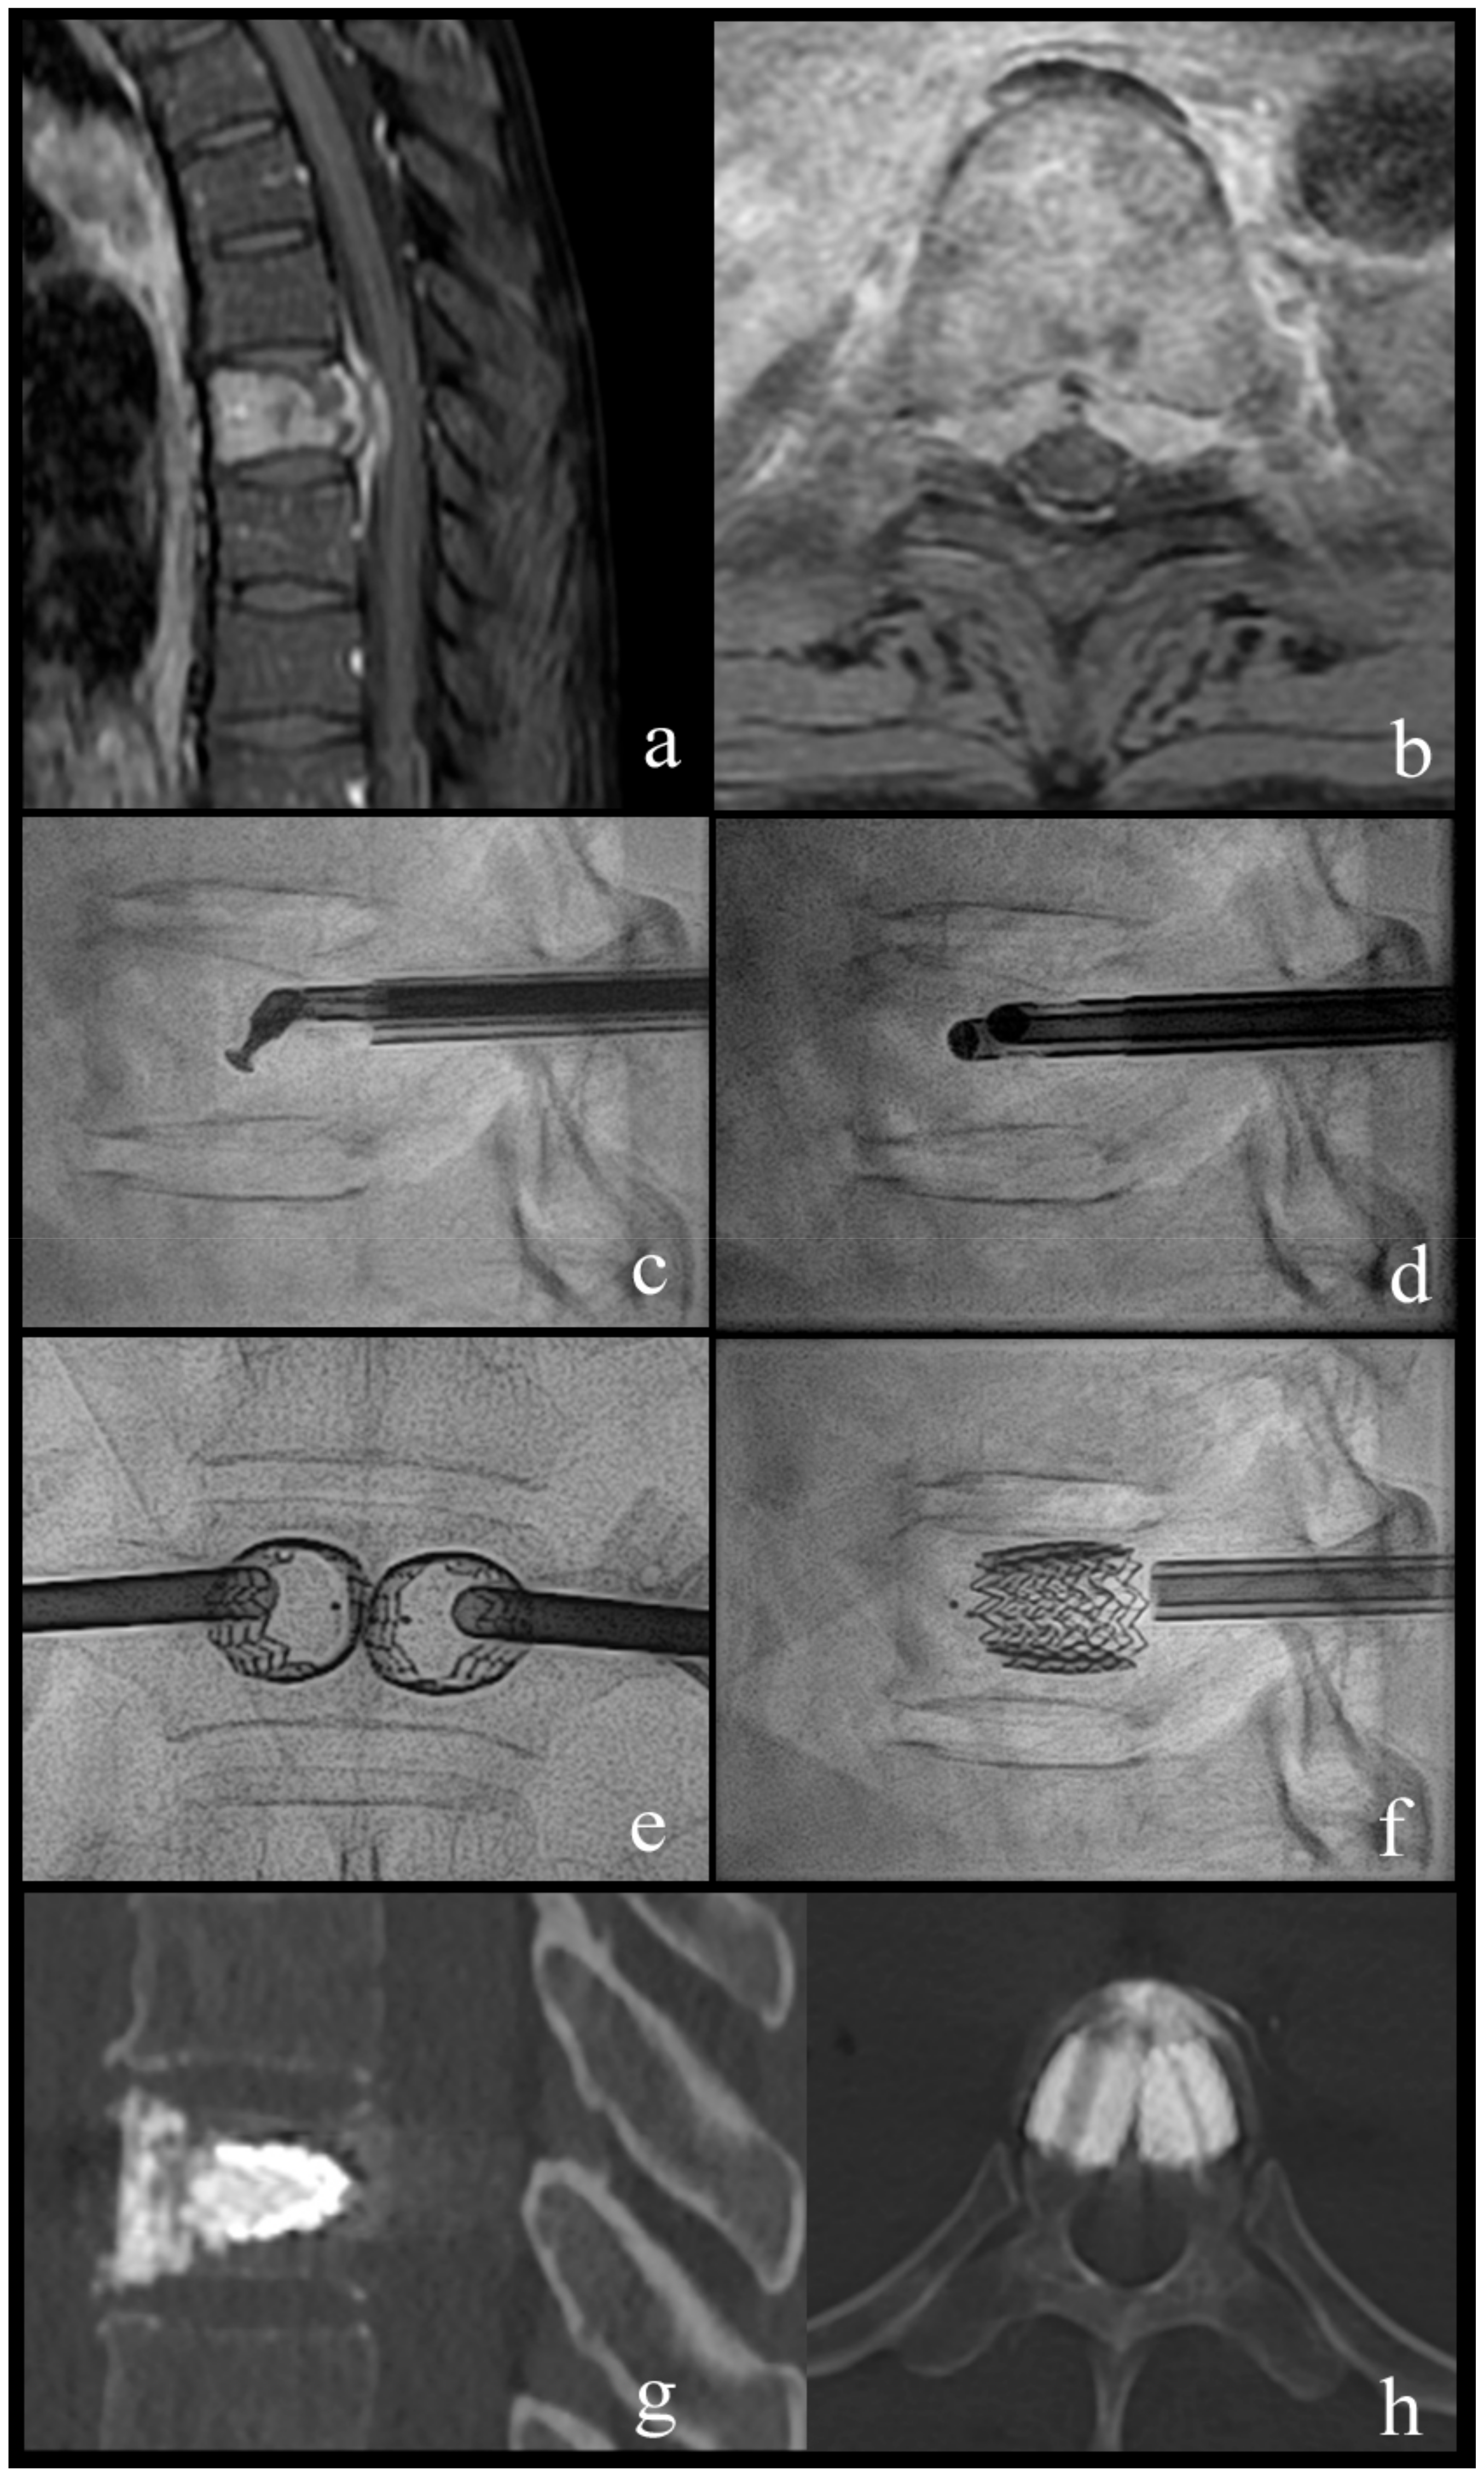

Figure 2.

Case 1; a 63-year-old woman with breast cancer and newly diagnosed bone metastases. (a,b) sagittal and axial T1-weighted fat-suppressed enhanced MR images show vertebral lesion with involvement of the posterior wall and an epidural mass. (c) lateral fluoroscopy view with angulated coaxial curette in the vertebral body for lesion fragmentation and cavity creation. (d) lateral fluoroscopy view after introduction of two 10 G cannulas into the fragmented lesion for tumor flush and aspiration. (e,f) lateral and anteroposterior fluoroscopy views after vertebral body stenting (VBS) deployment with height restoration of the fractured vertebral body. (g,h) sagittal and axial CT after VBS and cement augmentation.